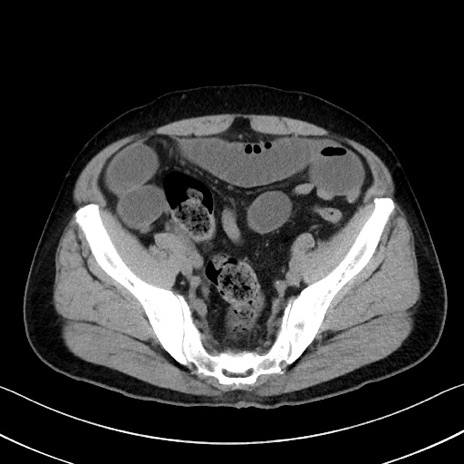

症例35(横断像)

【症例】70歳代 男性

【主訴】腹部膨満、嘔吐

【現病歴】昨日より腹部膨満感出現。本日増悪し、仙痛出現。嘔吐あり、受診。

【既往歴】糖尿病、胆摘後

【身体所見】BP 149/80mmHg、HR 74/min、BT 35.9℃、腹部:膨満、軟、圧痛なし。腸雑音減弱あり。上腹部正中切開瘢痕あり。

【データ】WBC 13500、CRP 1.72